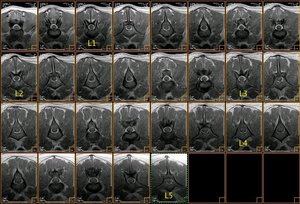

Resonancia magnética (SE T1 sagital) de la columna lumbar |

La médula espinal acaba en L5, donde empieza la cola de caballo |

Resonancia magnética lumbo-sacra de pastor alemán |